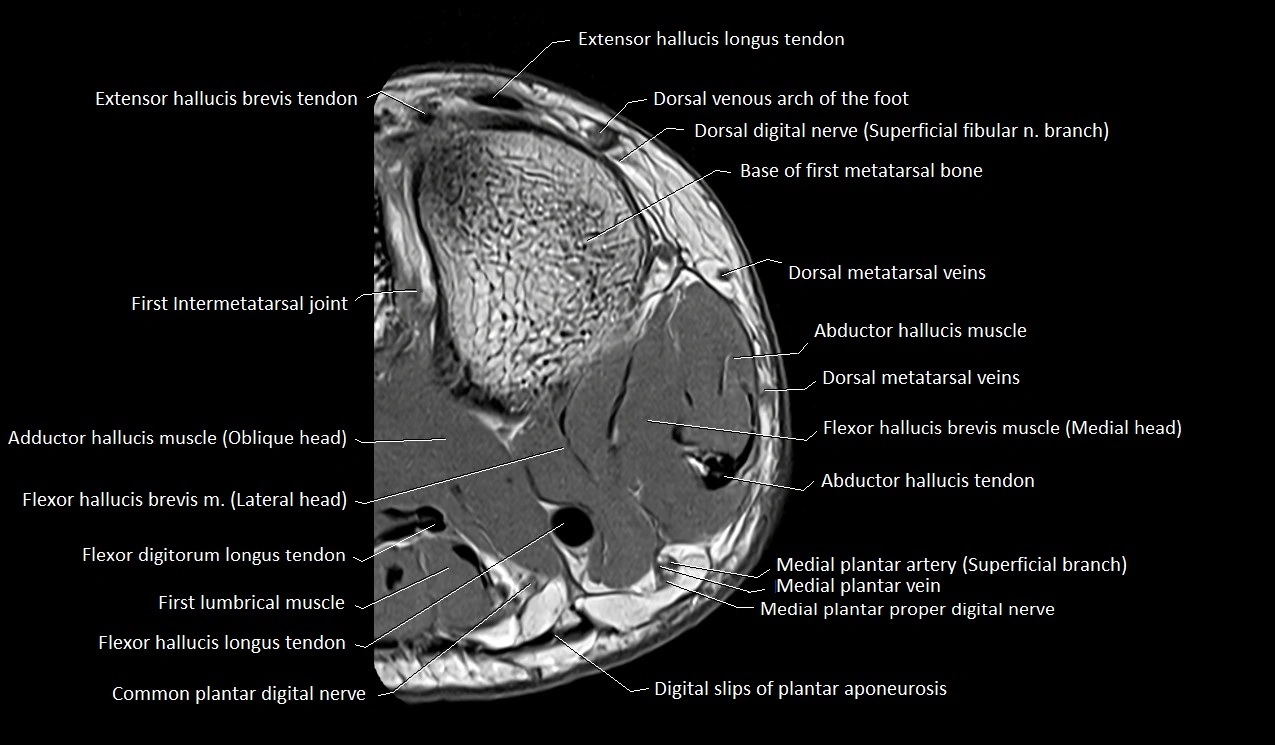

MRI image

image